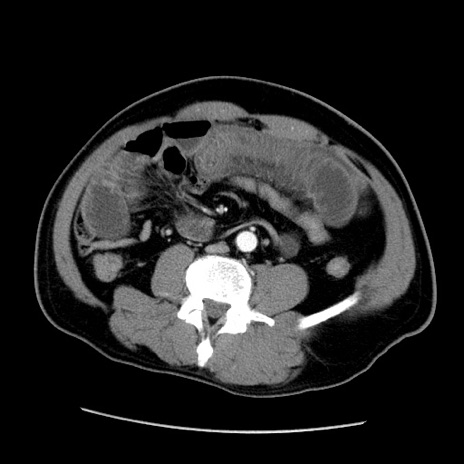

冠状断像

【症例】50歳代男性

【主訴】腹痛

【現病歴】AVMからの被殻出血のため回復期リハ病棟入院中。 本日午後3時頃急に下腹部痛が出現した。

【既往歴】AVM、被殻出血、虫垂炎、高血圧

【身体所見】意識晴明、左半身不全麻痺、会話の理解は良好、36.5°C、腹部:膨隆、全体に板状硬、下腹部正中に圧痛点あり、反跳痛-、筋性防御不明、右下腹部にope scar

【データ】WBC 9400、CRP 0.06